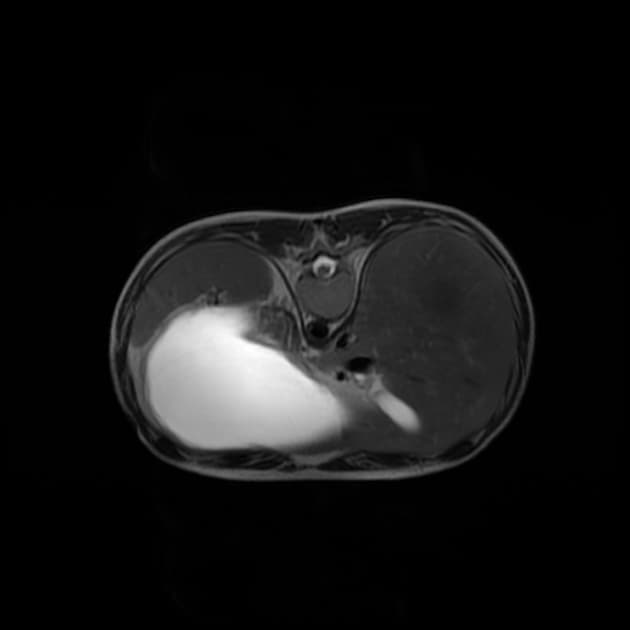

- Ruột non giãn đến 3,5 cm đường kính, có mức hơi-dịch, không thấy điểm chuyển tiếp rõ ràng. Có mức hơi-dịch ở đại tràng ngang, mức nhỏ ở đại tràng lên. Nhiều đoạn hồi tràng cho thấy thành tăng quang mạnh, dày đến 9 mm. Có hiện tượng tăng lưu huyết và vân mỡ quanh các đoạn này. Các hạch bạch huyết mạc treo vùng phản ứng không to. Lượng nhỏ dịch tự do trong ổ bụng gần khu vực này. Các hình ảnh này gợi ý rất nhiều đến bệnh Crohn đang hoạt động (active Crohn disease).

Trường hợp này minh họa sự tồn tại đồng thời của bệnh Crohn và viêm cột sống dính khớp — hai tình trạng có liên quan qua cơ chế miễn dịch di truyền chung, đặc biệt là dương tính với HLA-B27. Các dấu hiệu trên CT như dày thành hồi tràng rõ rệt, tăng quang mạnh, vân mỡ quanh ruột và hạch mạc treo không to là đặc trưng của bệnh Crohn đang hoạt động. Việc không thấy điểm chuyển tiếp làm giảm khả năng tắc ruột cơ học. Đồng thời, các thay đổi xương như hẹp khớp cùng chậu hai bên, dính khớp và nhiều dây chằng vôi hóa khẳng định chẩn đoán viêm cột sống dính khớp. Mối liên hệ giữa bệnh viêm ruột và các bệnh khớp cột sống đã được xác định rõ, với tới 20% bệnh nhân Crohn phát triển viêm khớp trục. Các thuốc kháng TNF như adalimumab hiệu quả trong điều trị cả hai bệnh, nhấn mạnh tầm quan trọng của việc nhận diện đồng thời hai bệnh lý này trong thực hành lâm sàng.